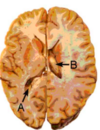

Label A & B

A: Floccus B: Tonsil

Identify structure A Stria terminalis Anterior commissure Fornix Corpus callosum Posterior commisure

Identify structure A Stria terminalis Anterior commissure **Fornix** Corpus callosum Posterior commisure

138

dentify the arrowed structure uncus optic nerve olfactory gyrus midbrain Wernicke’s area

The pathology shown in this image is Left tonsillar herniation Right tonsillar herniation Left uncal herniation Right uncal herniation Left subfalcine herniation Right subfalcine herniation

The pathology shown in this image is Left tonsillar herniation Right tonsillar herniation **Left uncal herniation** Right uncal herniation Left subfalcine herniation Right subfalcine herniation